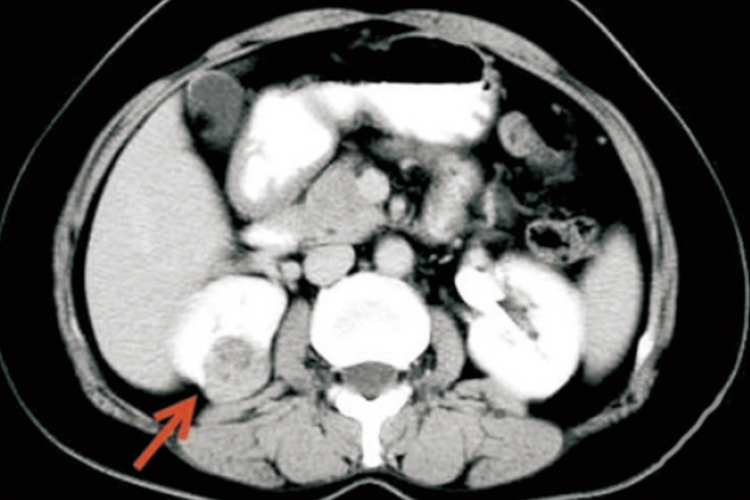

良性肾肿瘤常见于肾血管平滑肌脂肪瘤,症状多不明显,常见的症状体征包括腰痛、血尿、腹部肿块及大的错构瘤突然破裂所致低血容量性休克等。CT是最有效和可靠的诊断手段,肾错构瘤内含大量脂肪组织及血管、平滑肌。其CT表现为低密度,CT值为负。